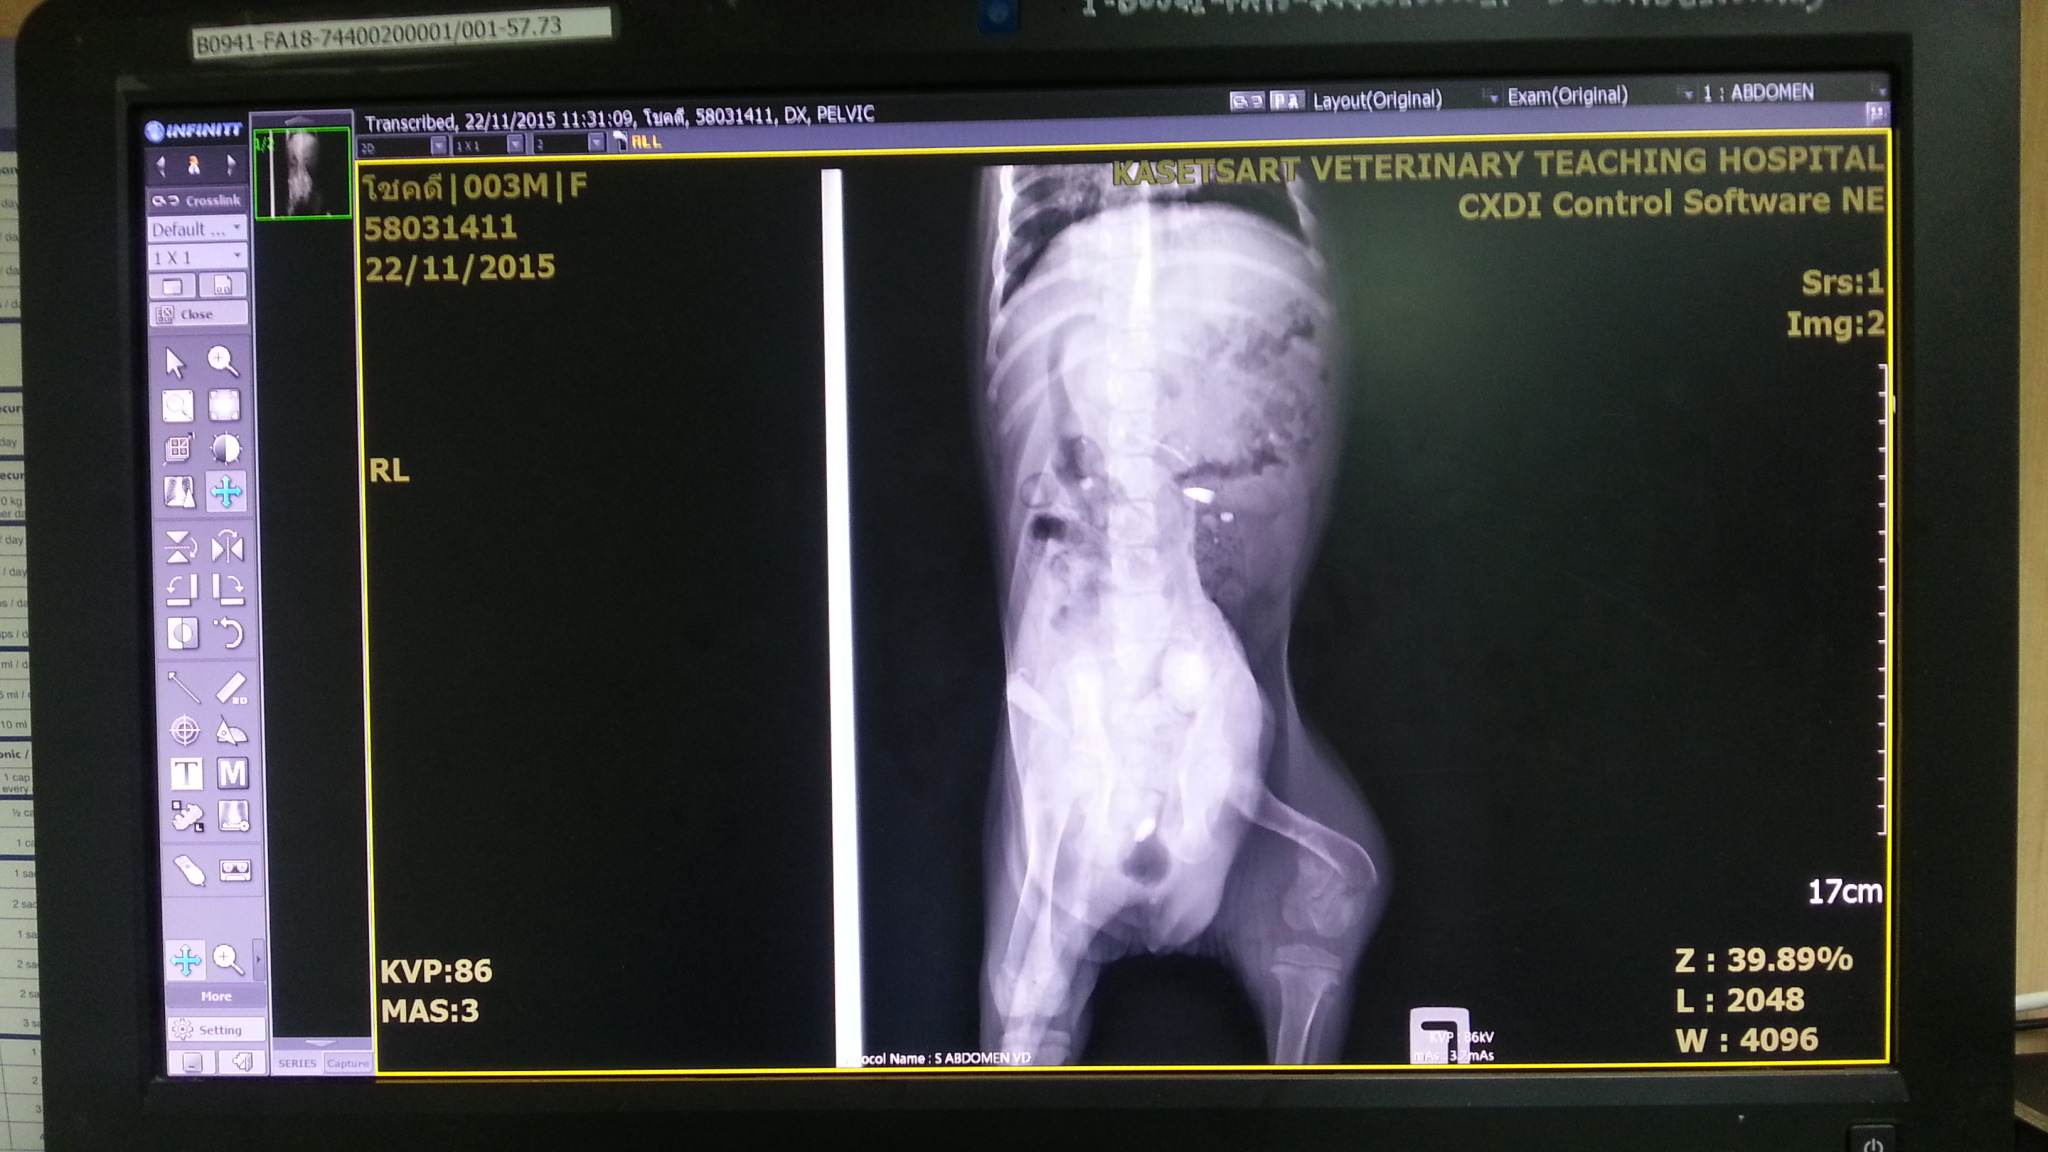

อาการคือ ช่องท้องด้านในเปิด ลำไส้และกระเพาะปัสสาวะ ออกมาจากช่องท้อง แต่ยังอยู่ในผนังหน้าท้อง (ตามรูป) กระดูกเขิงกรานหัก กระดูกขาหลังซ้ายหัก

รูปประกอบ